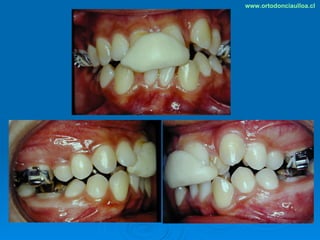

Este documento presenta dos casos clínicos de pacientes que recibieron tratamiento de ortodoncia. El primer caso fue de una paciente femenina de 14 años con apiñamiento dental y mordida cruzada que fue tratada mediante extracción de premolares y alineamiento dental. El segundo caso fue de un paciente masculino de 14 años con clase II esqueletal y desarmonía dentomaxilar que fue tratado con extracción de premolares y corrección de mordida. Ambos casos mostraron mejoría después de 3 años de tratamiento.